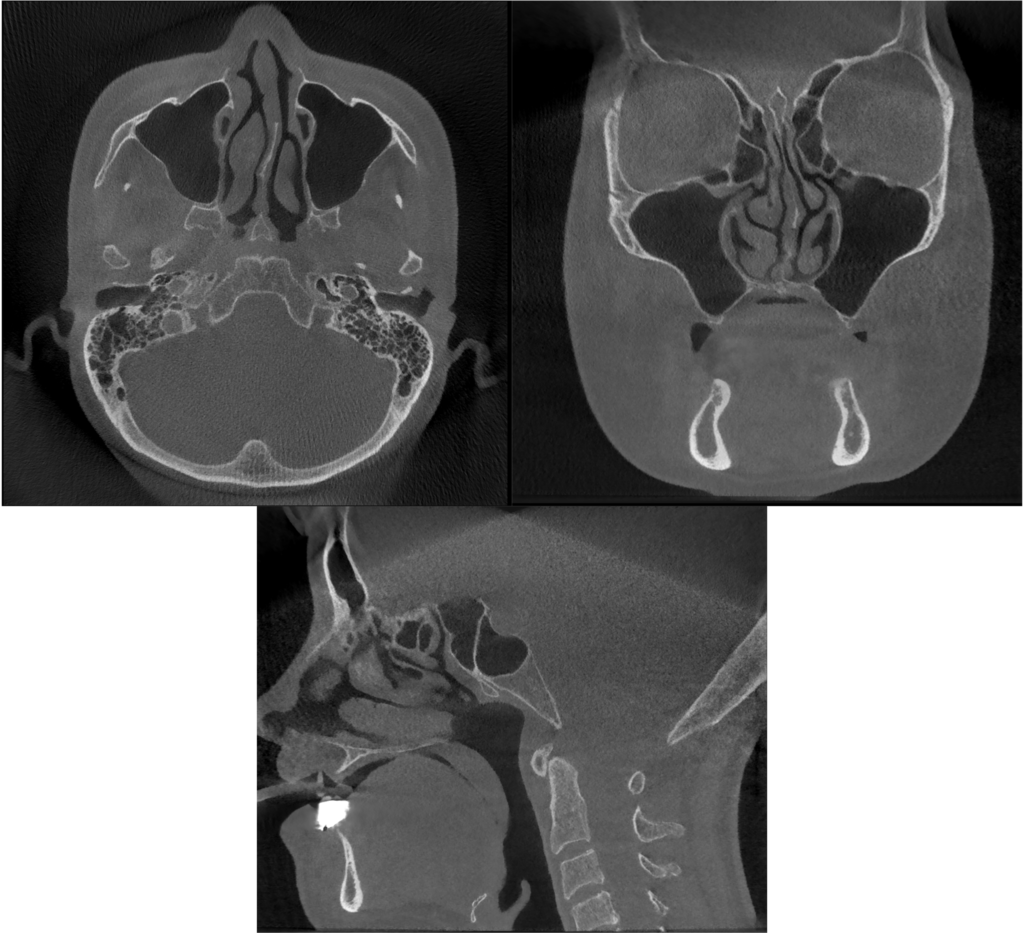

Bedrossianの分類より、ZoneⅠ〜Ⅲいずれにも十分な骨を認めないことから、Insufficient Boneと判断ができ、ノーマルインプラントは困難であることが考えられる。上顎はAll-on-4のためにはザイゴマインプラントが4本必要であることが考えられる。下顎は十分な歯槽骨量があることから、ノーマルインプラント4本を埋入することが可能であると考えられる。また、上顎のザイゴマインプラントの埋入に関しては、 ZAGA分類のType3とType4が混在しているため、ザイゴマインプラントが困難であることが予想される。